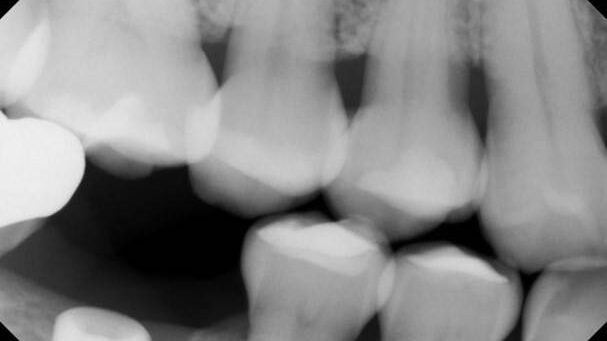

Latrogenic Inclusion of Impression Material Resulting in an Early Abutment Screw Fracture. The patient presented for retrieval of a fractured abutment screw from a Straumann 4.8 BL implant in the #19 site.

The patient presented on referral form Dr. S. for retrieval of a fractured abutment screw from a Noble Active 3.5 implant in the #29 site.